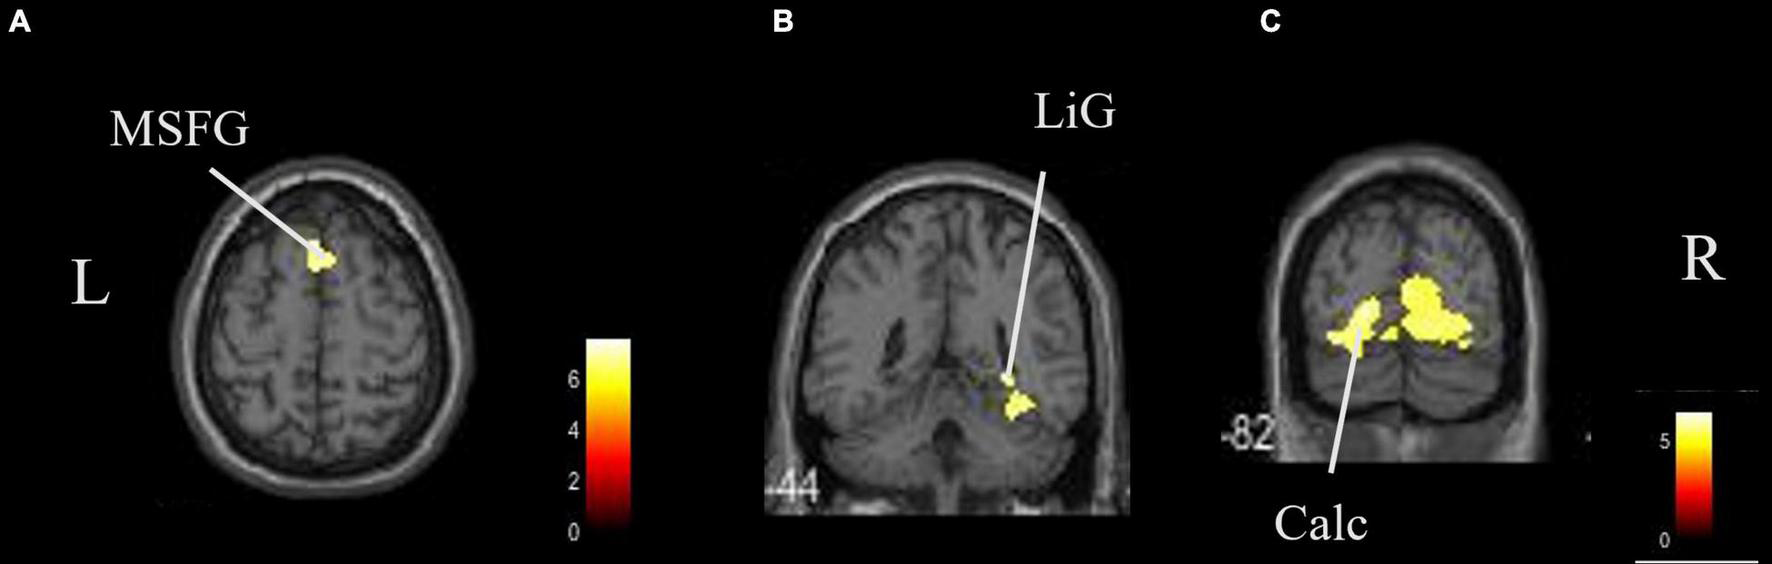

The coordinates of the areas that were significantly activated while listening to classical music are listed in Table 3 and depicted in Figure 2. Significant activation was observed in the right middle frontal gyrus (MFG) and left thalamus proper while listening to classical music. The coordinates of the areas that were significantly activated during ASMR auditory stimulation are listed in Table 4 and depicted in Figure 3. Significant activation was observed in the left thalamus proper, left anterior insula, right triangular part of the inferior frontal gyrus, right cerebellum exterior, left accumbens, right amygdala, left medial superior frontal gyrus (MSFG), and left planum polare. Table 5 shows the coordinates of the areas that were significantly more activated by ASMR stimulation than by classical music. Images of the activated areas are shown in Figure 4. Significant activation was observed in the left calcarine cortex, right superior frontal gyrus medial segment, and right lingual gyrus during ASMR stimulation compared to classical music.

FIGURE 4

Brain areas that were significantly more activated by ASMR stimulation than by classical music. Significantly more activation was observed in the right triangular part of the left calcarine cortex, right superior frontal gyrus medial segment, and right lingual gyrus in ASMR compared with classical music. (A) Axial view. (B,C) Coronal view. L, left; R, right. ASMR, autonomous sensory meridian response; LiG, lingual gyrus; MSFG, superior medial gyrus medial segment.

In this study, we also identified the regions where ASMR stimulation induced a higher activation than classical music. These were the calcarine cortex, superior frontal gyrus medial segment, and lingual gyrus. Activation in the posterior part of the cerebrum is also related to auditory stimulation and is due to spatial hearing (Lewald et al., 2004). We think that ASMR has a more specific impact on the identification of location, direction, and distance of sound sources than classical music.

Particularly noteworthy is the activation of the superior frontal gyrus and the medial prefrontal cortex (mPFC), which is said to be the basis of social cognitive abilities (Feldman, 2012). The mPFC is thought to be activated because ASMR may contain many sound sources that are closely related to daily life and social activity. The mPFC region is also involved in the regulation of neurotransmitters such as dopamine, which projects to the prefrontal cortex through the dopamine pathway and has been shown to enhance stress resistance in response to short-term stress (Tanaka et al., 2012). It also involves the release of oxytocin, which is a stress-reducing, pro-social neuropeptide that is effective in modulating brain activity in depressed individuals (Pincus et al., 2010). These neurohormones are known to induce feelings of comfort, relaxation, and drowsiness (Lochte et al., 2018). ASMR stimulation is thought to be more effective in inducing relaxation and reducing stress than classical music because it activates brain regions associated with these functions.